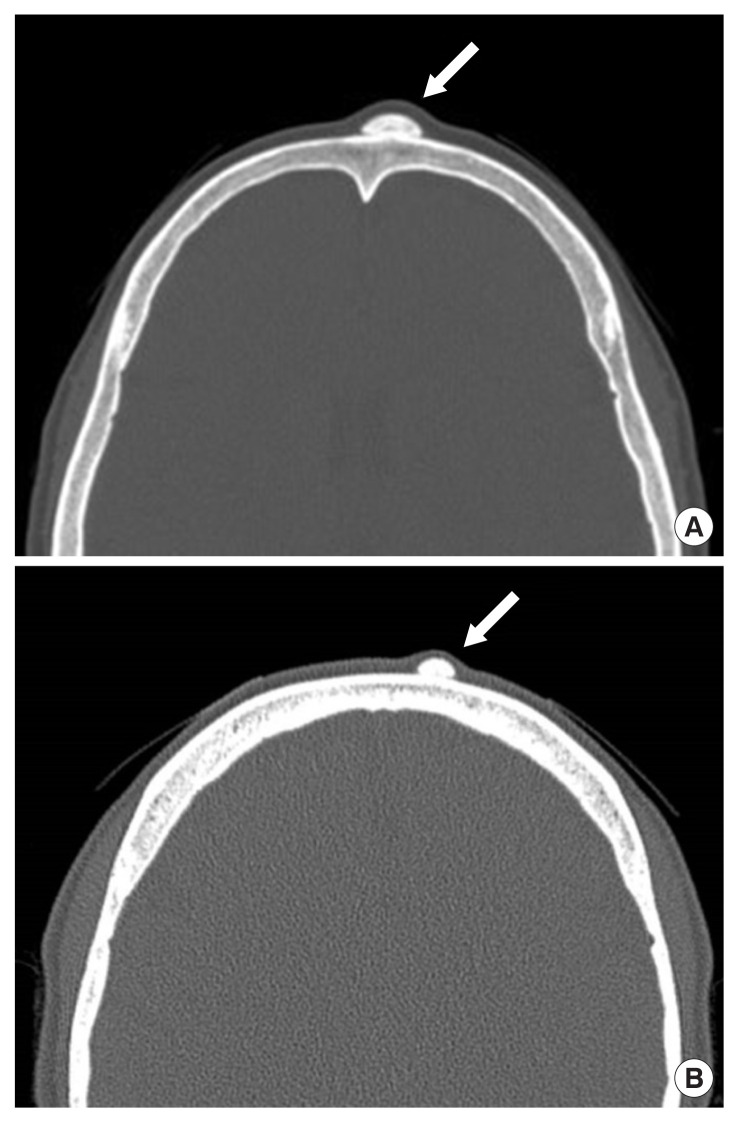

We retrospectively reviewed the medical records of patients who visited our hospital with frontal peripheral osteomas between January 2014 and June 2022. We analyzed the following variables: age, sex, type, single or multiple, size, history of head trauma, operation, and recurrence. It was classified into sessile and pedunculated types according to the shape detected on facial bone computed tomography (Fig. 1).

Fig. 1.

Computed tomographic scans of the head revealing: a sessile frontal osteoma (arrow) (A) and a pedunculated frontal osteoma (arrow) (B).